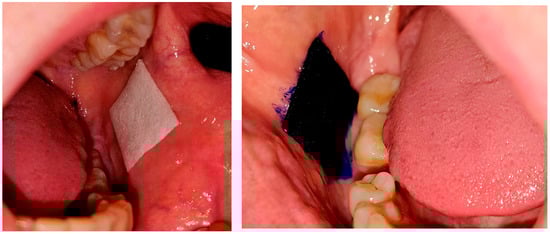

- Carriers with clobetasol and methylene blue.